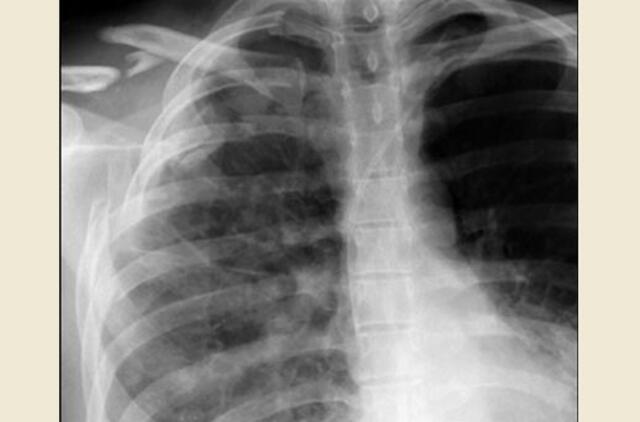

40-metis pareigūnas dėl dešinės pusės 6-ojo šonkaulio lūžimo, suteikus medicinos pagalbą, gydosi namuose.